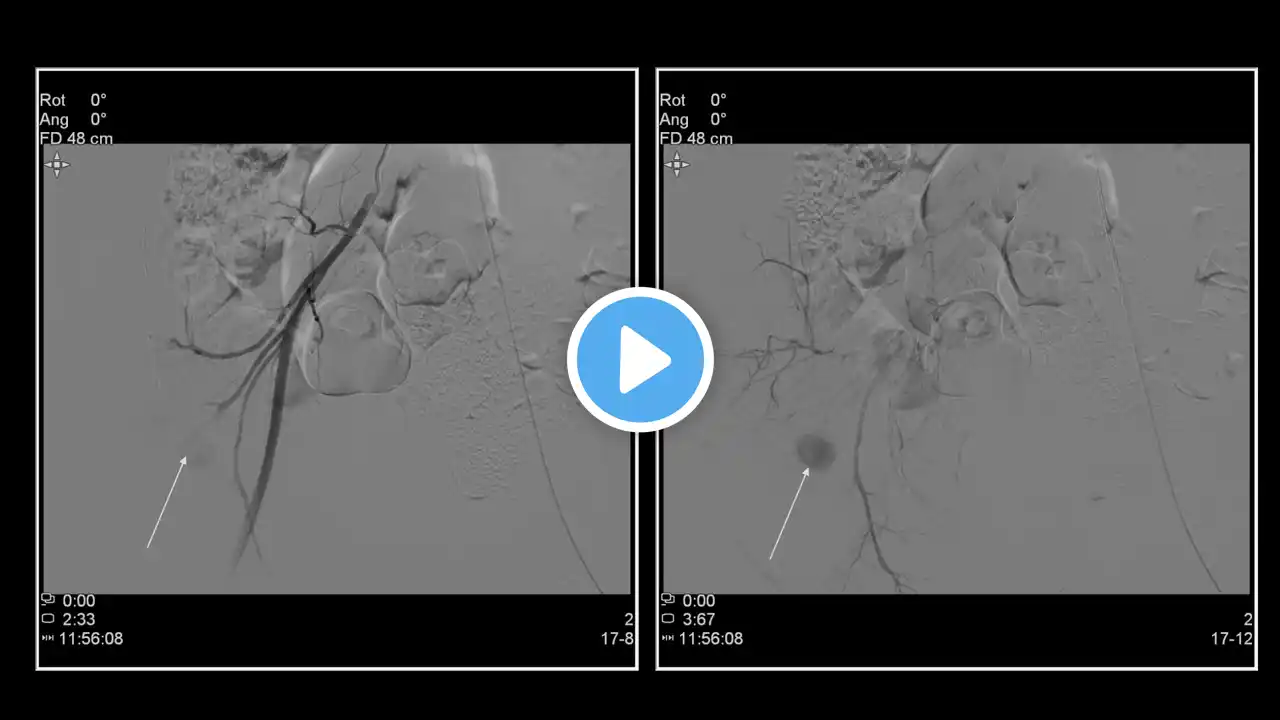

Bronchial and systemic artery glue embolization for massive recurrent hemoptysis using nBCA (n-butyl cyanoacrylate) in a young female patient with damaged right lung | AIIMS Patna | Interventional Radiology